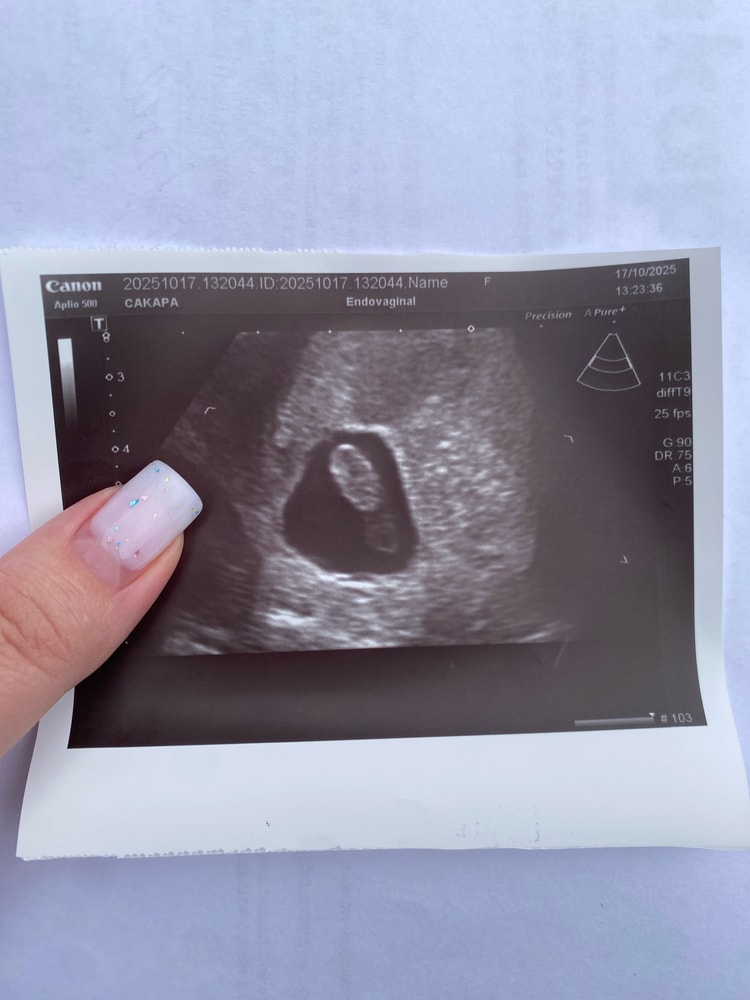

У нас ПОЛУЧИЛОСЬ!!! (Финальный тест, пожелания)У нас все получилось! Девочки, желаю всем увидеть заветные две полосочки. У всех все получится🥰 мои тесты начали показывать чуть заметную полоску только на 5 день задержки, на 8 день задержки появилась полоска уже поярче. Когда я выкладывала сюда свои тесты на 3 день задержки(был призрак) писали: ждите месячные, реагент, для 3 дня задержки слишком бледная полоска, и тд. Пост с такими комментариями я удалила, т.к. была очень растроена и комментаторы показались мне слишком злыми)Но в глубине души я верила, что оно то самое. Девочки, надежда есть всегда, только верьте и все получится🥰 сейчас срок 7-8 недель, хотя по месячным должно быть 9 недель. Во время узи сказали, что с малышом все хорошо. К слову, я не знала свой ДПО, и месячные у меня были регулярными. Скорее всего, была поздняя овуляция или позднее прикрепление, что пояснил врач)